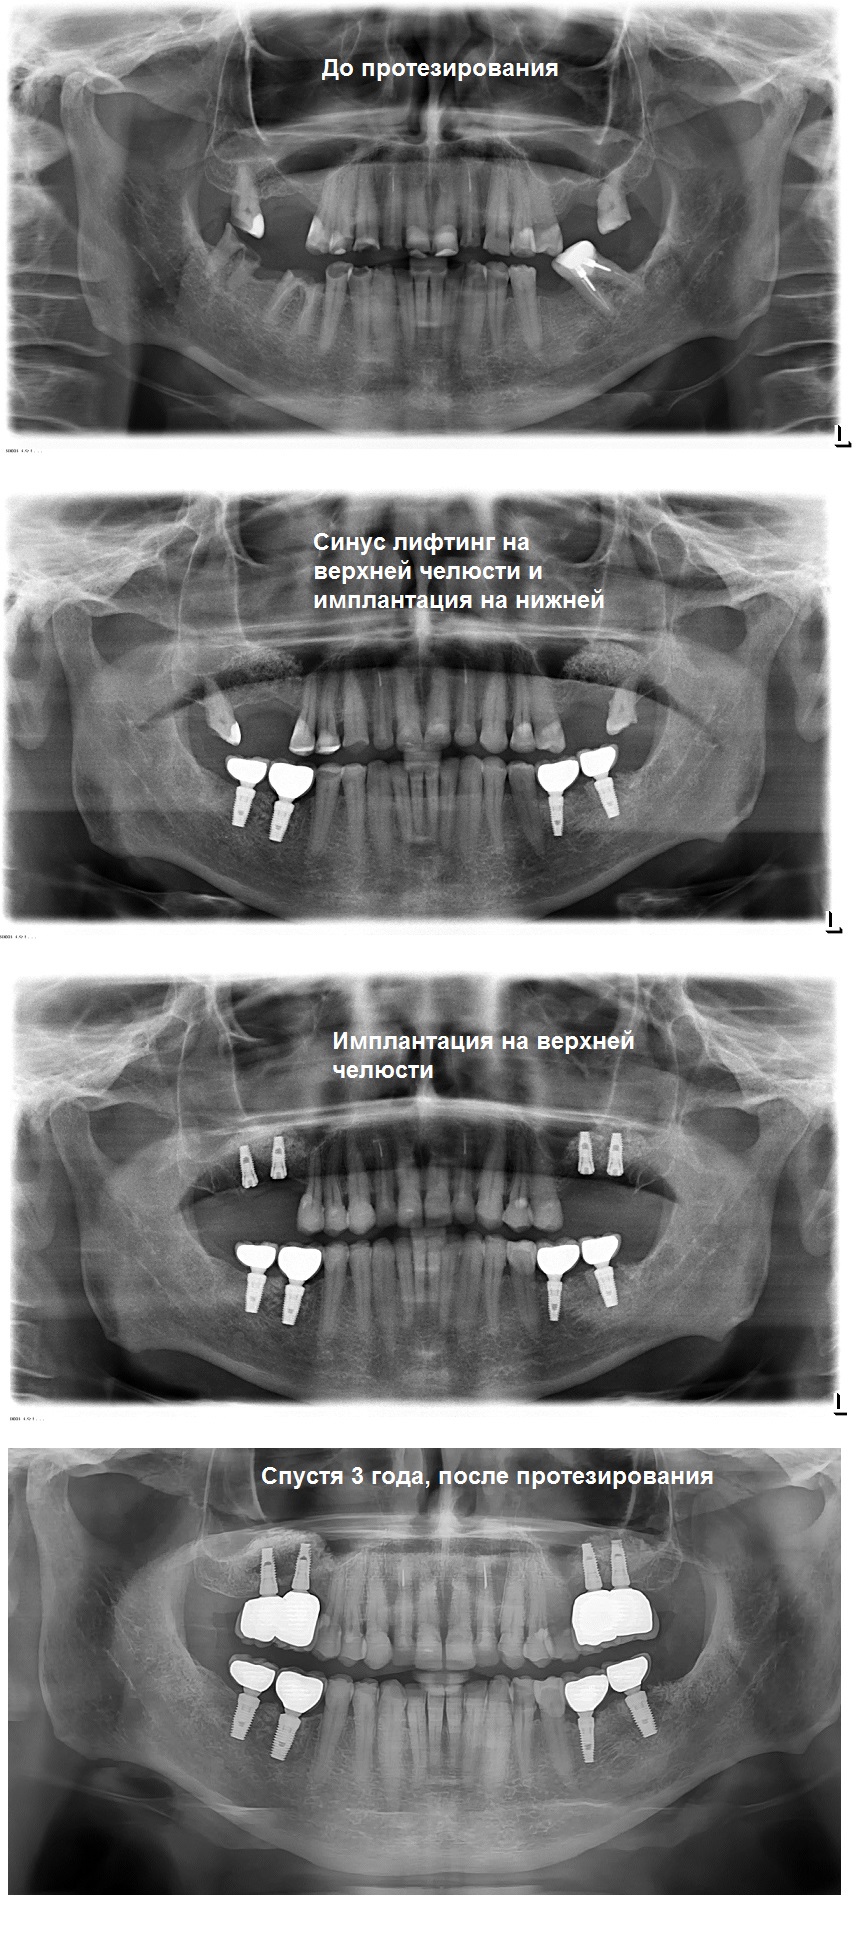

Протезирование на имплантантах

В

задней области верхней челюсти, замена зуба с

помощью зубных имплантатов, зачастую, требует хирургической операции по пазухе.

Эта операция представляет собой форму предварительной протезной

хирургии для повышения качества и количества кости в задней области

верхней челюсти. Предварительная оценка верхней челюсти необходима для успеха этой операции.

Если количество костей, между гребнем и полостью, является недостаточным, (<5 мм), то необходима процедура открытого синусового подъема ( синус лифтинг).

В представленном случае была сделана , как раз такая операция на верхней челюсти перед установкой имплантов.